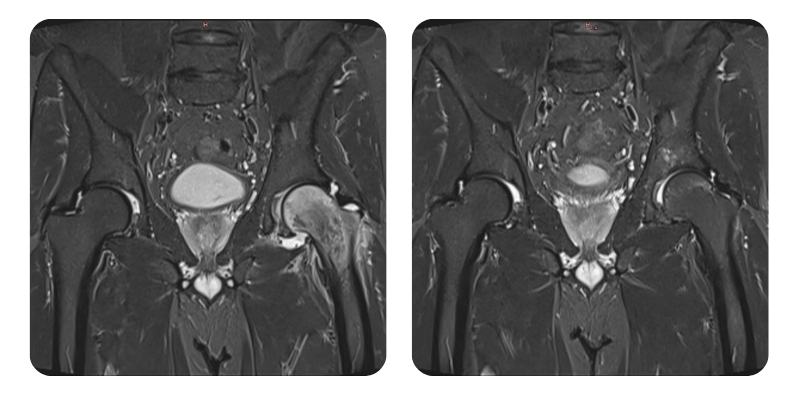

Before

After

J.A.V., 43 years old - Left femoral head edema

Diagnosis: Left femoral head edema.

Therapeutic interventions: 20 hyperbaric therapy sessions.

A reduction of over 90% in edema is observed, correlated with clinical improvement, and the patient is considered recovered.